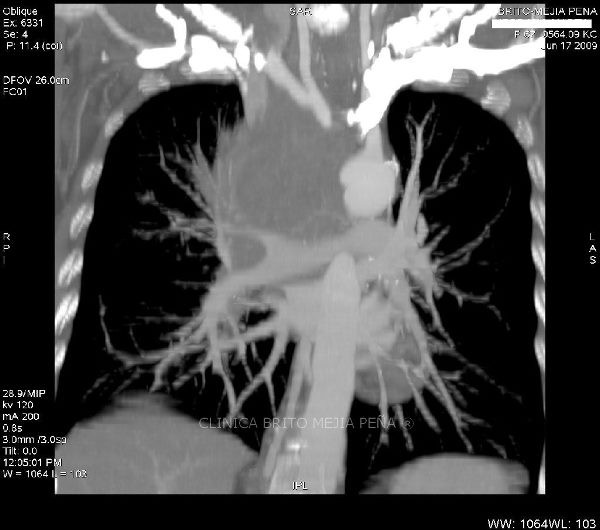

Trombosis arteria pulmonar axial